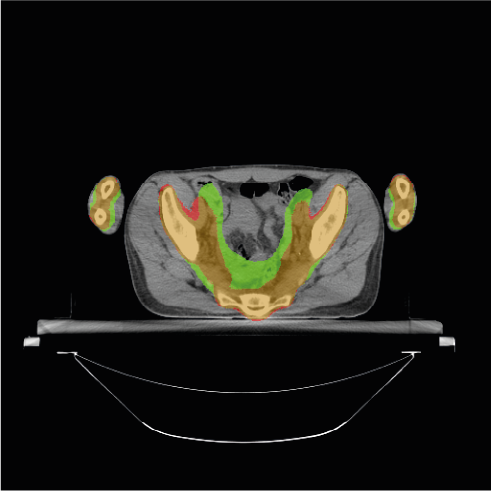

To further understand the areas where the models do not accurately segment the PTV, we provide some visual examples of the poor segmentations Figure 4. The first row of the Figure 4 shows four examples of slices poorly segmented by the BCEL model. The first slice (Figure 4a) corresponds to the head and neck area. The segmentation error in the left and right areas of the head (i.e., the green areas) may be due to conservative segmentation of the second level of neck lymph nodes in the ground truth. The standard reference point for segmenting these lymph nodes might be a slightly higher slice, but the radiation oncologist likely included the target on this slice due to the large CT thickness of 5 mm. The second slice (Figure 4b) shows an absence of hepatic portal lymph nodes. This area is subject to high anatomical variability, and due to the lack of contouring guidelines [38] in the early years of data acquisition, this area was often omitted by the radiation oncologist. In the third slice (Figure 4c), the absence of the pre-sacral lymph nodes (anterior to the sacrum) is evident. Moreover, the predicted segmentation of the external iliac lymph nodes is inaccurate. This target area is defined by adding a margin to the iliac vessels. In the fourth slice (Figure 4d), representing the legs area, the prediction fails to segment the inguinal lymph nodes, likely because these are frequently omitted by physicians. The second row of the Figure 4 shows the same slices overlayed with the predictions of the DL model. Notably, the segmentation errors of the DL model closely resemble those of the BCEL one, previously discussed. Please notice that the segmentation mistakes of DL model are very similar to the ones of the BCEL model, previously discussed. Nevertheless, a higher propensity for false negatives is discernible in the DL model’s segmentations, evidenced by the larger green regions surrounding the bones in Figure 4h and within the iliac lymph node area in Figure 4g.